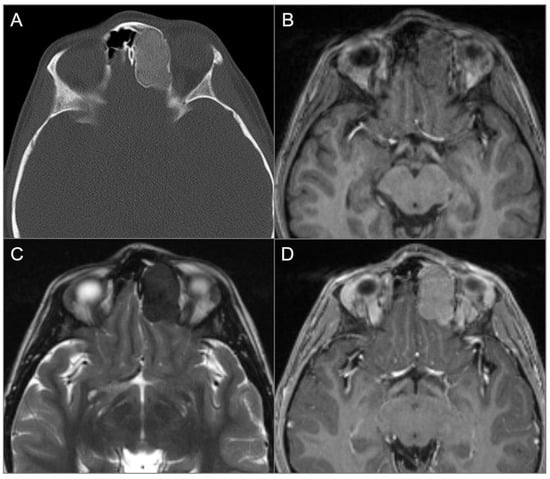

4.2.1. Ossifying Fibroma

4.2.2. Osteoma

4.2. Anterior Skull Base Tumors